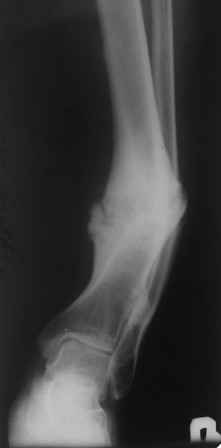

Больной 33г, лечится в течение 2-х лет, выходил на работу. Первоначально, был выполнен остеосинтез двумя шурупами с дополнительной фиксацией перелома наружной гипсовой повязкой. Снята преждевременно в поликлинике, через 3 месяца после операции, постепенно возникла варусно-рекурвационная деформация.Больному был наложен АВФ, с постепенной устранением деформации. Демонтаж АВФ через 4 месяца. Спустя 3 месяца появилась болезненность и стала нарастать деформация. В настояще время больной ходит с тростью, с полной нагрузкой на конечность. Имеется варусно-рекурвационная деформация 45-20 градусов. Болезненность при пальпации, незначительная подвижность в зоне перелома. Взгляды коллег разошлись: 1. Наложить АВФ с остеотомией м/б кости, постепенное исправление деформации, после, БИОС. 2.Наложение АВФ с остеотомией в зоне ложного сустава, коррекция деформации- постепенная, после исправления осей- БИОС. 3.Открытая репозиция перелома, одномоментное устранение деформации, БИОС.